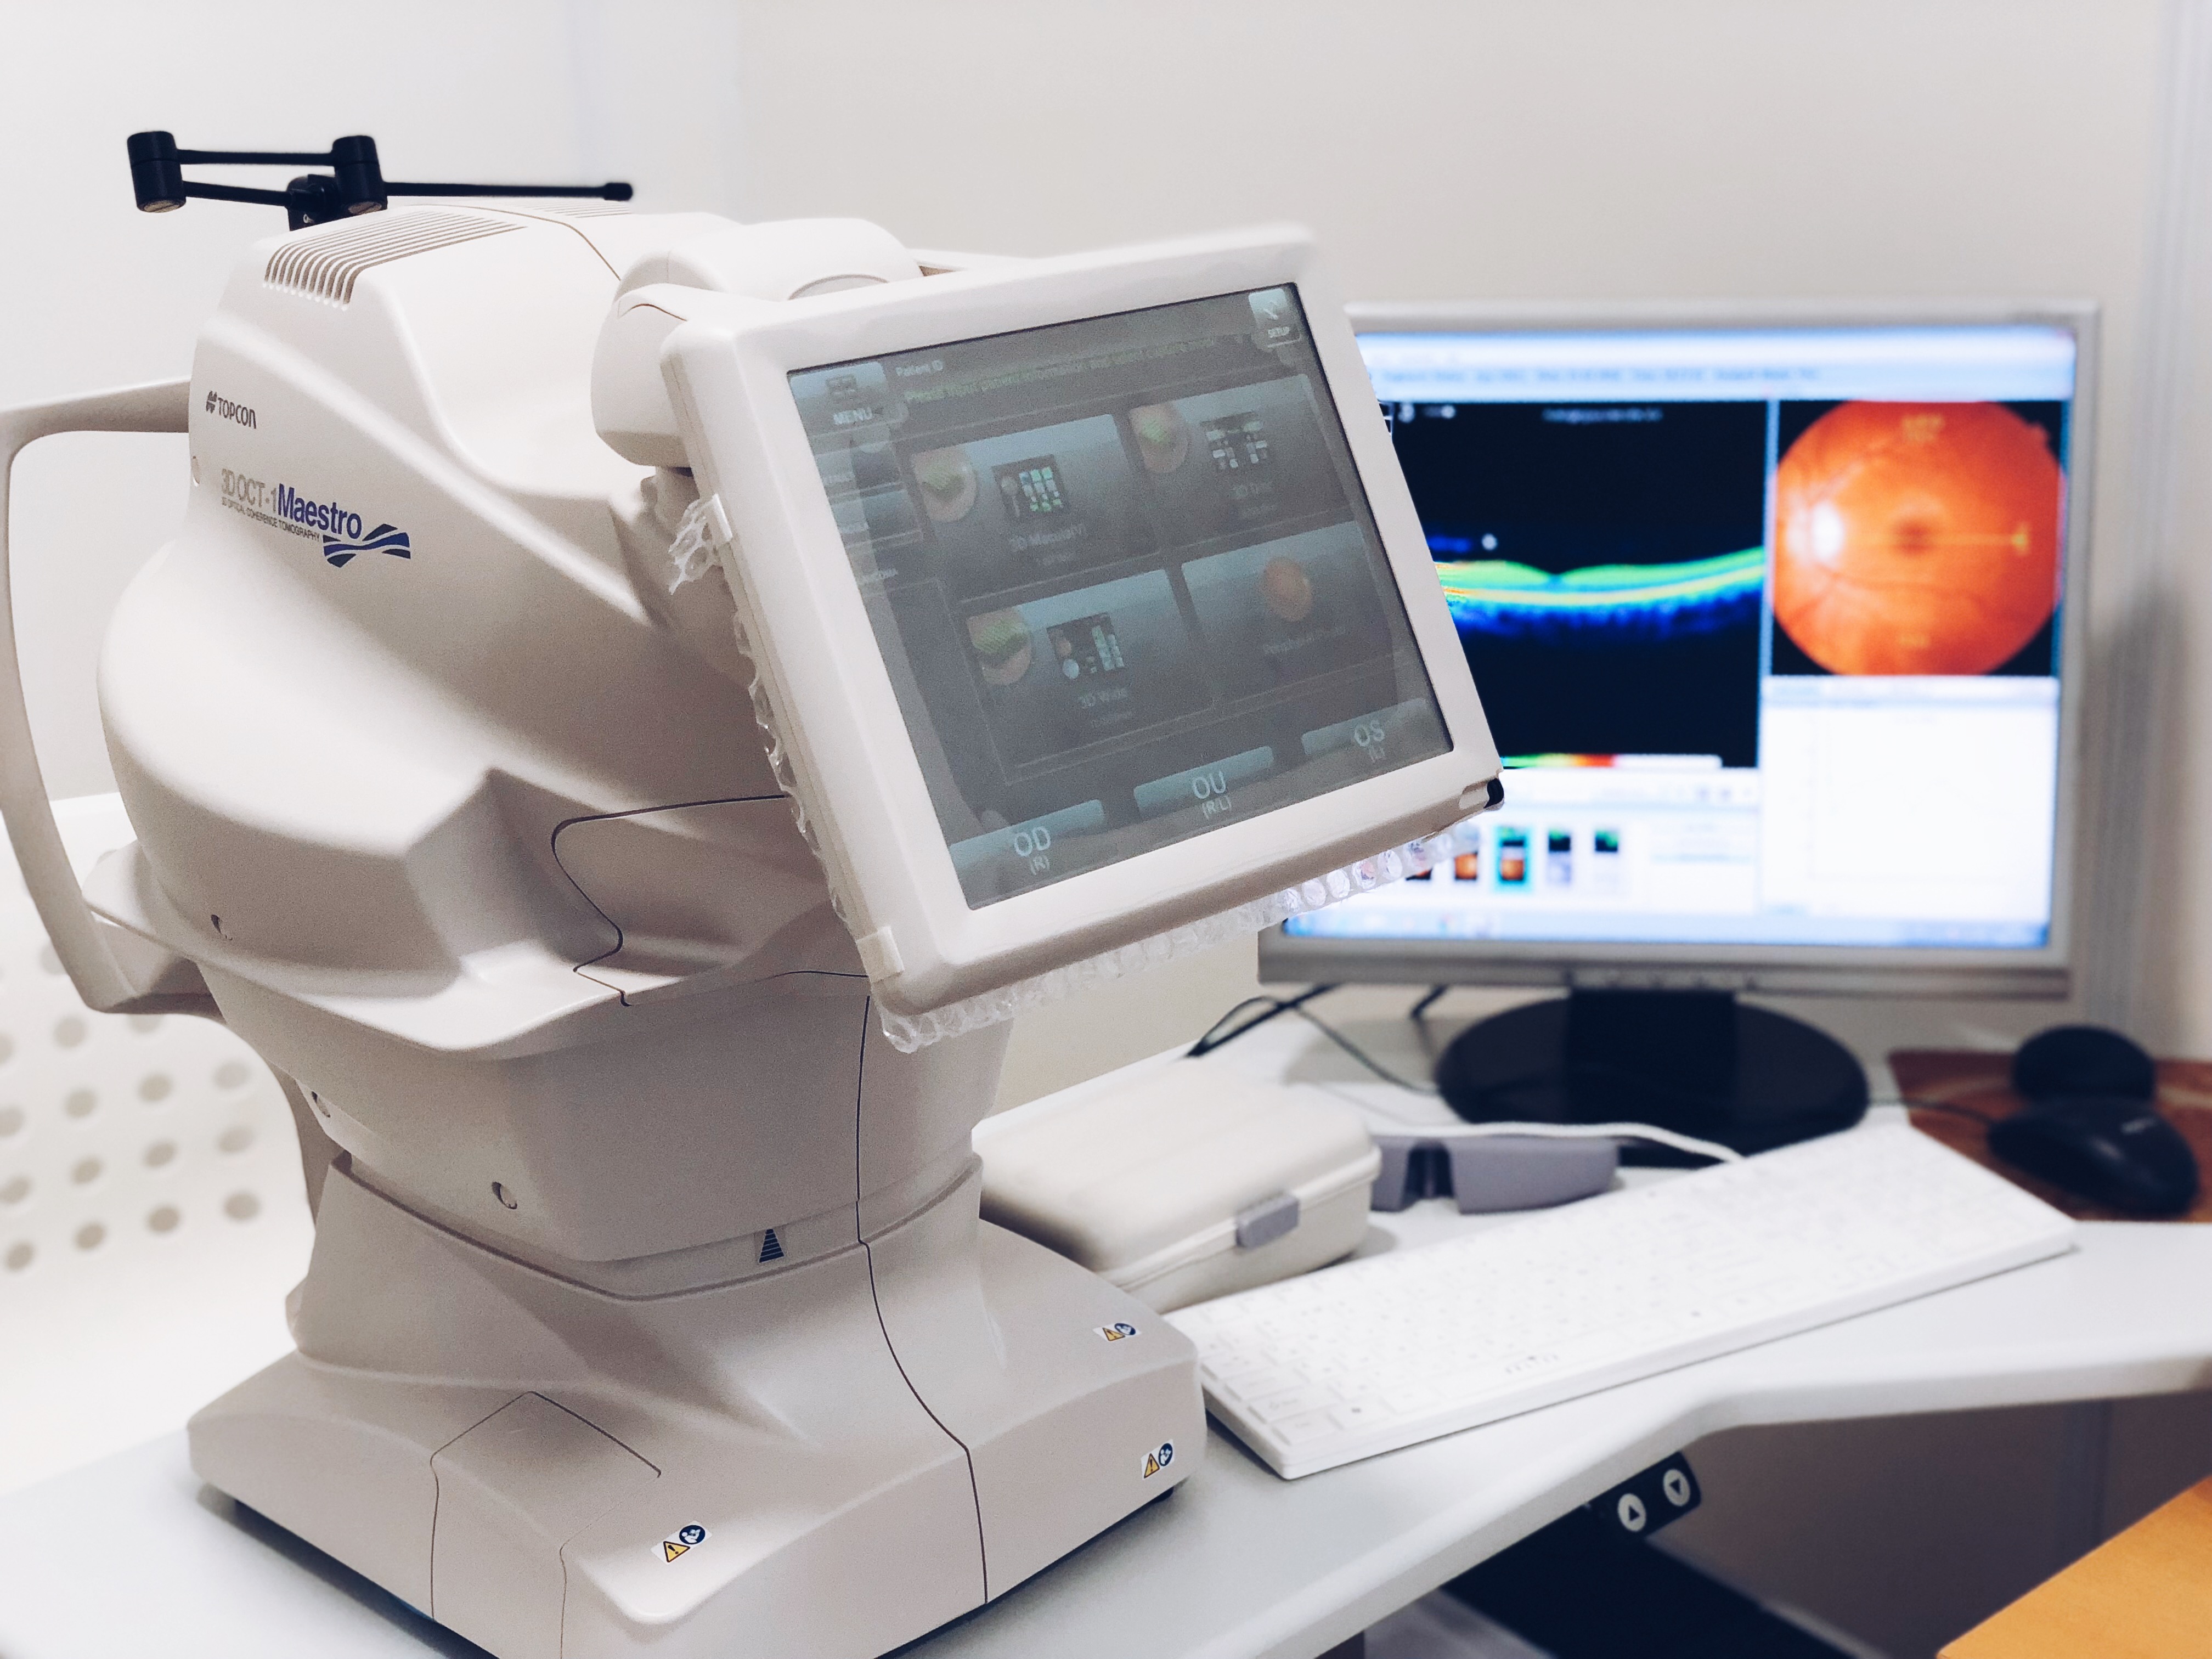

Раздел: Фотоальбом решений